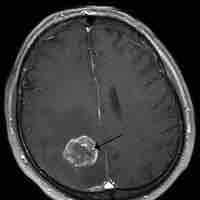

Thumbnail

Brain Tumors

A brain tumor is a pathological abnormal growth of cells in the brain.